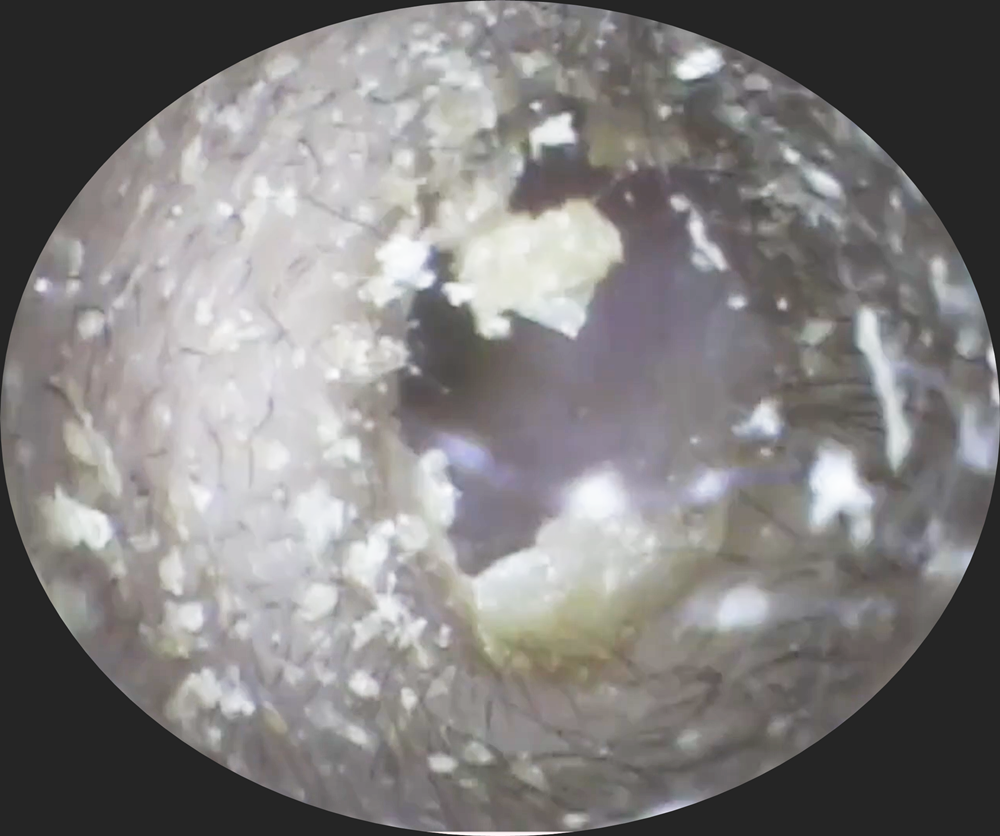

- 2026年1月13日vol.322・・お姉さんの耳の穴覗いていいですか?どれくらい溜まってる?・・仲良し姉妹earissへ行く♡

- 2026年1月5日vol.330・・サーファーズイヤーってしてますか?(茨城、千葉の砂入り)

- 2025年12月8日vol.328・・中学生もお耳痒いんです!!(リピーター様のお嬢様♡)